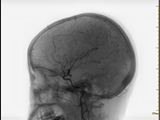

颅内动脉瘤,俗称“脑内不定时炸弹”,是脑动脉壁薄弱处鼓出的“小血泡”。它人群发病率高,绝大多数平时毫无症状,但一旦破裂,会导致致命的蛛网膜下腔出血。首次破裂死亡率高达30%-40%,幸存者中近半数会遗留偏瘫、认知障碍等严重残疾。其最大风险在于破裂出血,表现为突发的“雷霆样”剧烈头痛,具有极高致死率和致残...2025-11-20 点击数:21